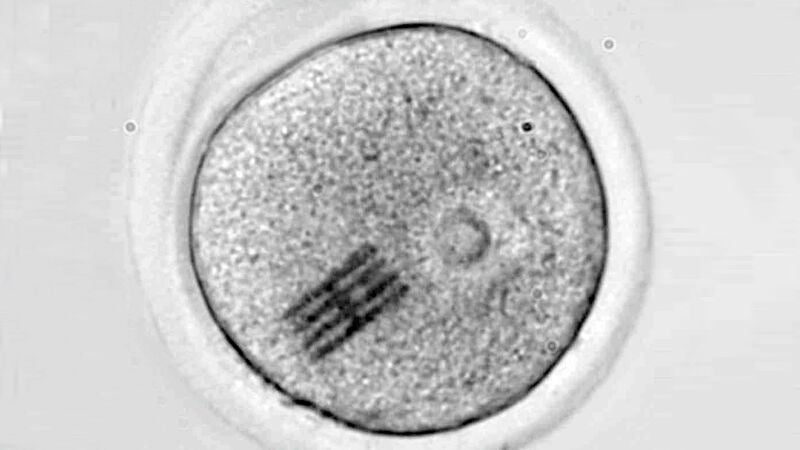

Los análisis se realizaron mediante microscopía infrarroja por láser (LDIR), tras un proceso de mineralización para eliminar componentes orgánicos. Como medida de control, se verificó que los recipientes utilizados no estaban contaminados previamente.

En más del 50 % de las muestras de fluido folicular se detectaron poliamida, poliuretano y polietileno. En el semen, el teflón apareció en el 56 % de los casos, mientras que otros microplásticos estuvieron presentes en proporciones menores. Otros estudios anteriores ya han demostrado la presencia de microplásticos en varios órganos humanos que aparentemente no suponen un riesgo grave para la salud, por lo que esta nueva información no ha sorprendido a los investigadores.